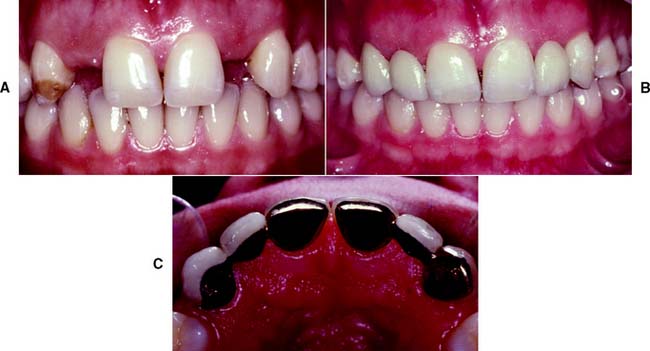

Anterior partial-coverage restorations can be fabricated to show no metal (Fig. 7-55), but their preparation requires considerable care. The facial margin is extended just beyond the highest contour of the incisal edge but not quite to the incisolabial line angle. Here the metal protects the tooth from chipping but is not visible.

Fig. 7-55 A, Teeth can be prepared for partial-coverage restorations that do not show any metal. Success depends on very careful margin placement. B, The incisal edge is not completely covered. The restoration margin is located between the highest point of the incisal contour and the incisofacial angle. C, Intact anterior teeth on either side of an edentulous space. D, Three-unit fixed dental prosthesis with pinledge retainers and a metal-ceramic pontic. E, Occlusal view of fixed dental prosthesis. F, Acceptable esthetic result is obtained.